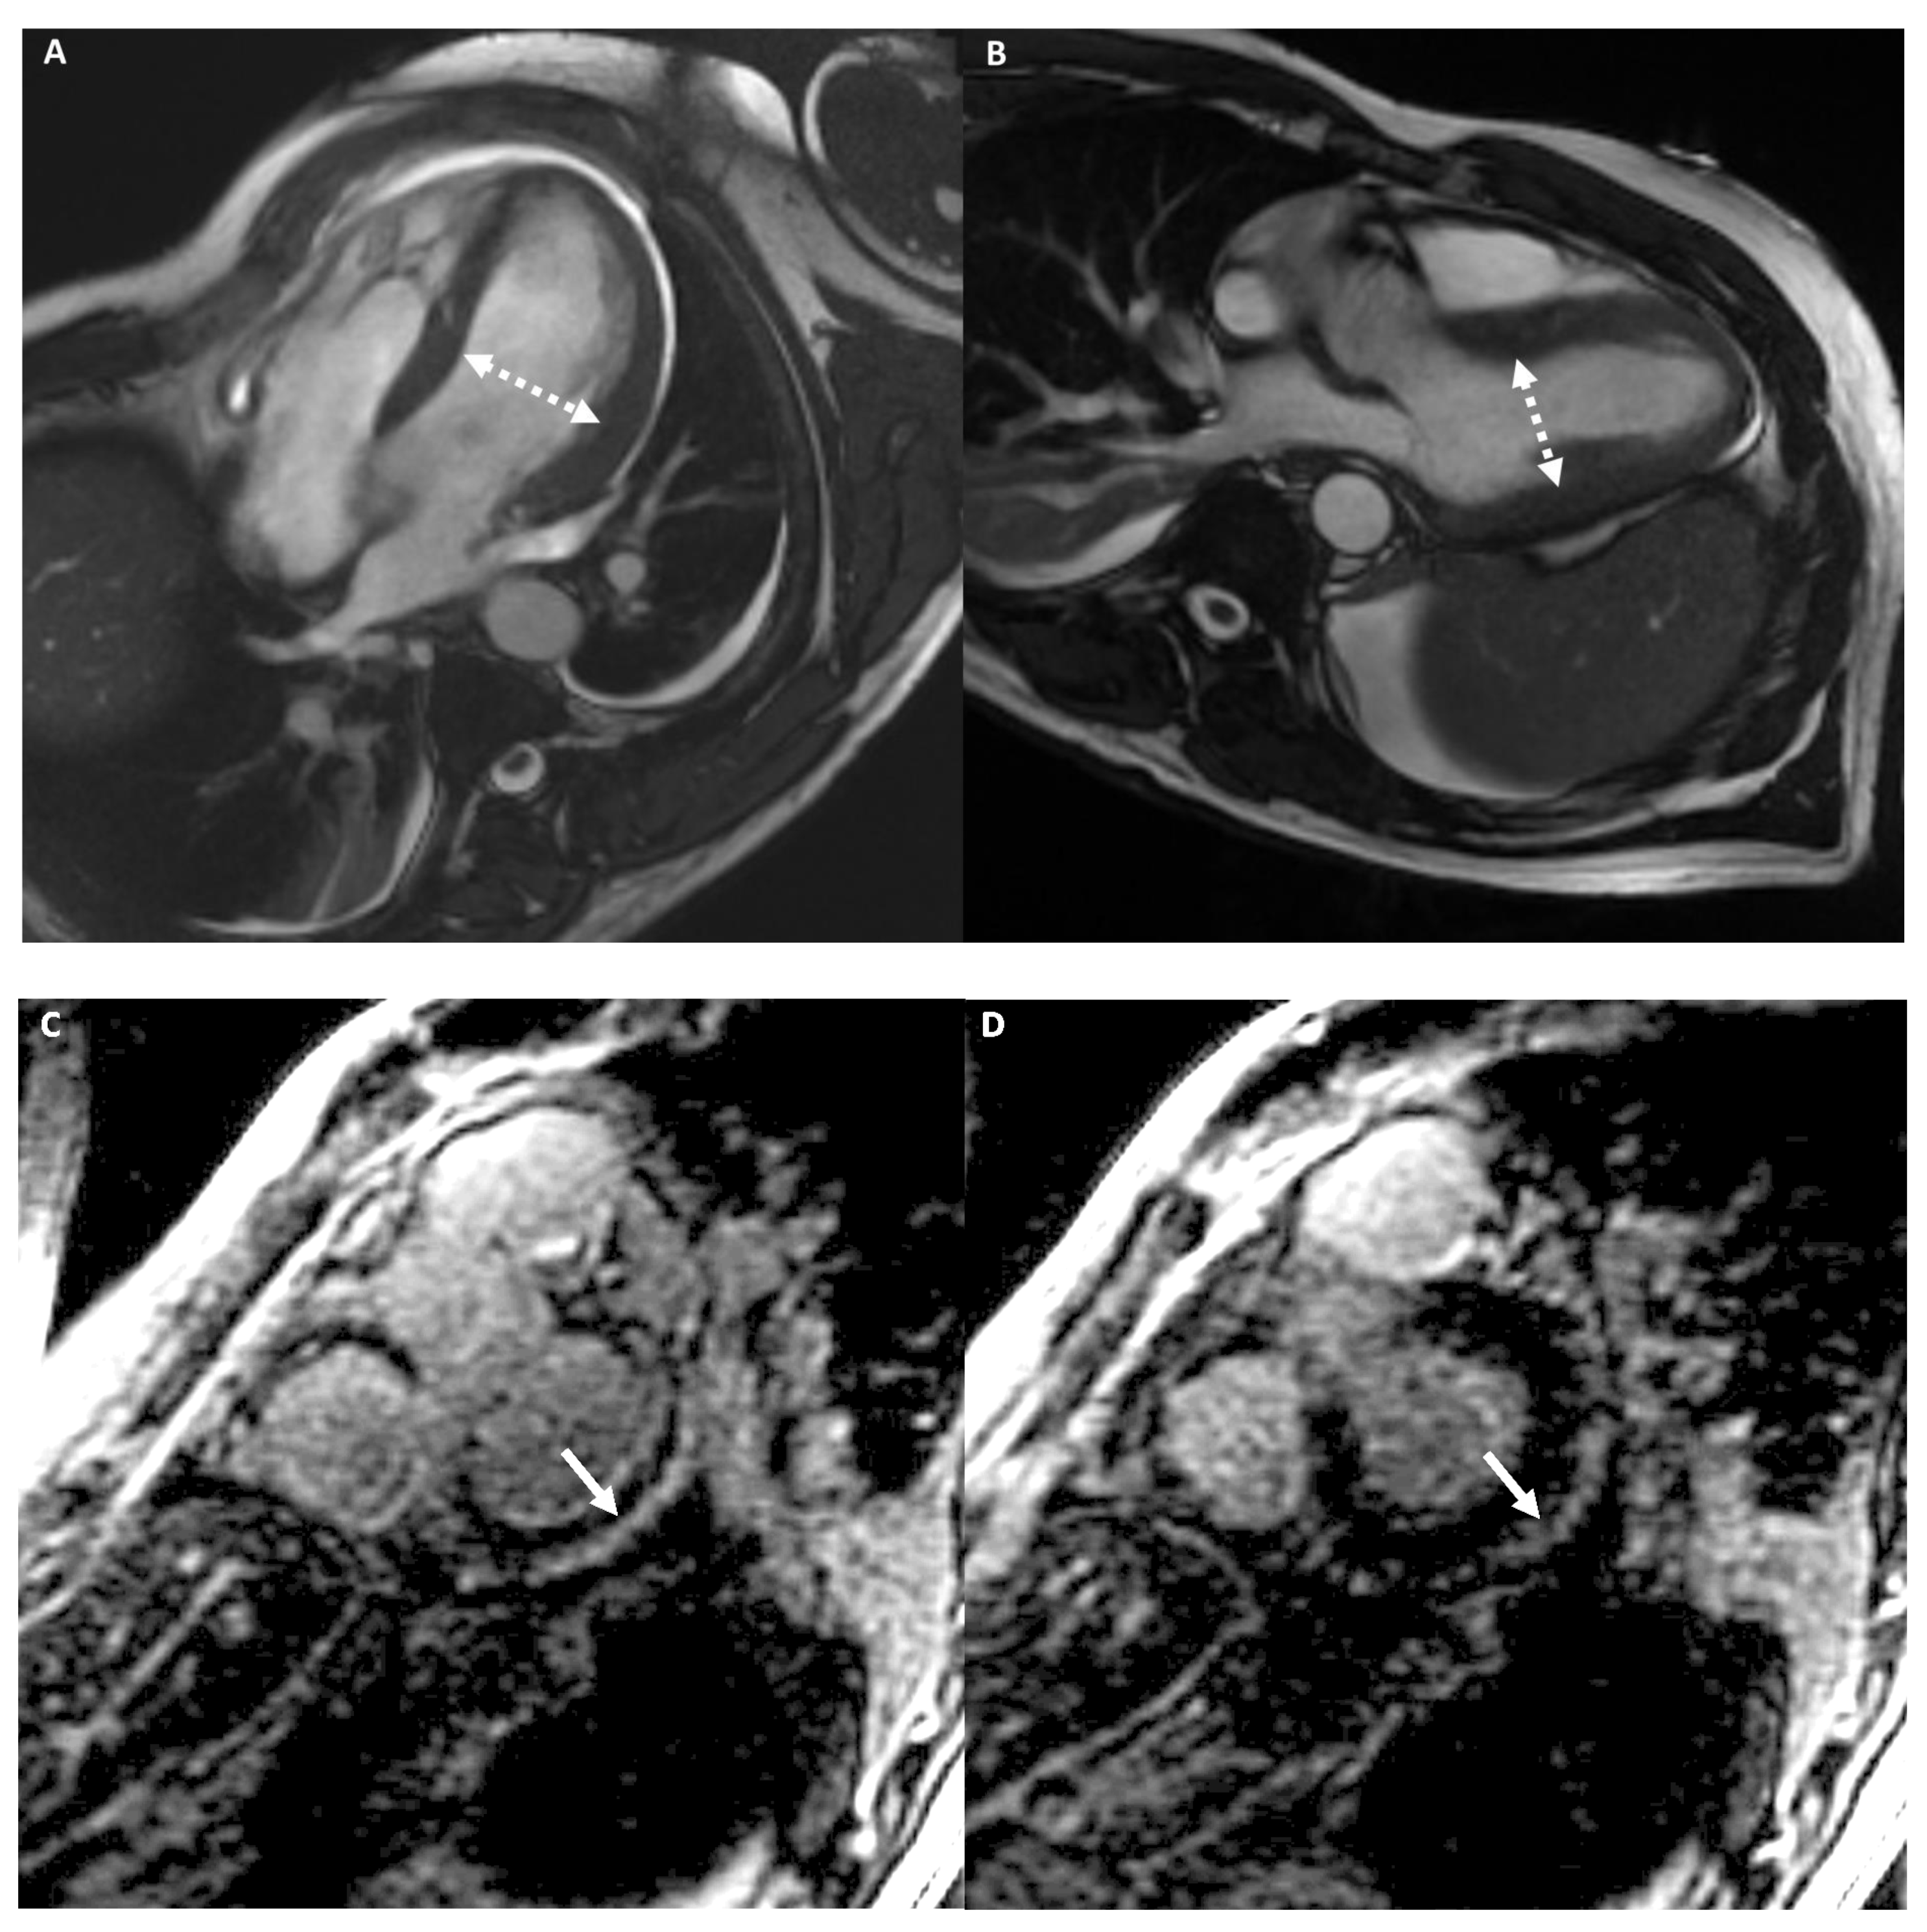

Left Dominant Arrhythmogenic Cardiomyopathy (LDAC)

- Palumbo, P.; Cannizzaro, E.; Di Cesare, A.; Bruno, F.; Schicchi, N.; Giovagnoni, A.; Splendiani, A.; Barile, A.; Masciocchi, C.; Di Cesare, E. Cardiac magnetic resonance in arrhythmogenic cardiomyopathies. Radiol. Med. 2020, 125, 1087–1101. [Google Scholar] [CrossRef]

- Miles, C.; Finocchiaro, G.; Papadakis, M.; Gray, B.; Westaby, J.; Ensam, B.; Basu, J.; Parry-Williams, G.; Papatheodorou, E.; Paterson, C.; et al. Sudden Death and Left Ventricular Involvement in Arrhythmogenic Cardiomyopathy. Circulation 2019, 139, 1786–1797. [Google Scholar] [CrossRef] [PubMed]